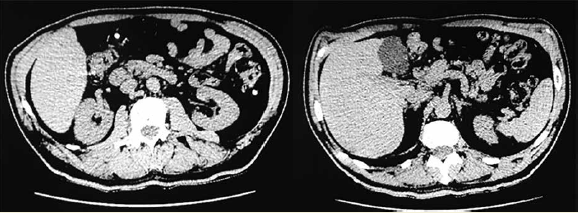

Inició con dolor tipo punzante a nivel de la región inguinal, asociado con un aumento de volumen, que desaparecía de manera espontánea, así como pérdida de peso no intencionada. En la exploración física se evidenció un defecto herniario, sin ninguna otra sintomatología asociada. Se realizó tomografía toracoabdominal como protocolo de ingreso, con el que se evidenció la presencia de una hernia inguinal derecha, así como una probable hipoplasia hepática del lóbulo izquierdo (figura 1).

Imagen: Núñez-Venzor et al.

Figura 1 Tomografía abdominal con corte axial en el cual se evidencia disminución en el tamaño del lóbulo izquierdo